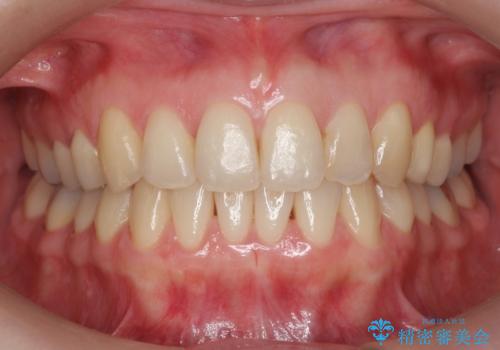

ワイヤーによる全体的ながたつきの矯正治療